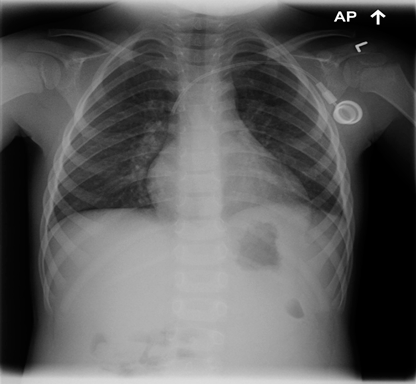

The following is a chest X-ray and CT-scan slide, showing the nice reexpansion of the left lung after few months of the surgery.

![]() Figure 13 |

![]() Figure 14 |